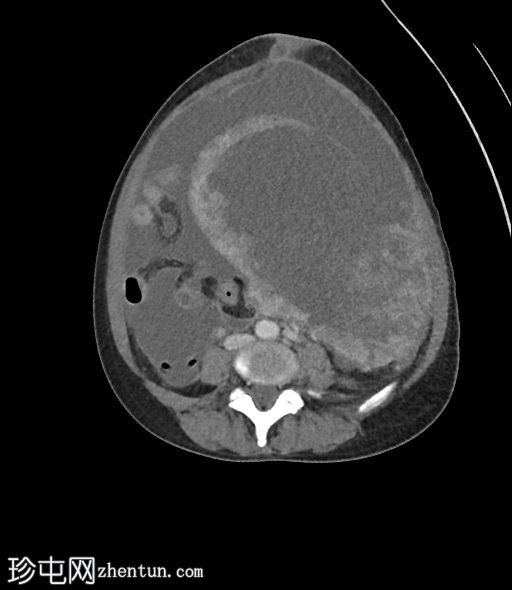

6个月前CT检查

CT

2.jpg

既往CT显示子宫内有多发性肌瘤,但在子宫右侧一个较大的肌瘤内可见一处不典型、中心低密度区。

无腹水。